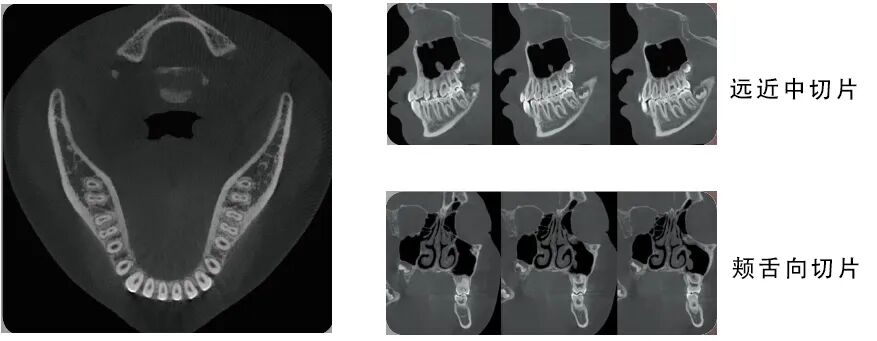

CT摄影

360°完整扫描,800帧超清影像,配合高性能CT算法,呈现细腻影像

C型臂可实现对患者头颅360°的完整扫描,最小体素尺寸0.05mm,分辨率可达2.2lp/mm,800帧超清拍摄,<60s重建时间,配合高性能算法精细重建,更适合牙体牙髓疾病的诊断。

朗视配套SmartV软件还可将采集到的数据进行多平面组合重建,不但可以同时观察到轴向面、冠状面和矢状面图像,而且可以在任意位置进行断层切面,同时获得颊舌向切片和远近中切片,方便医生诊疗。